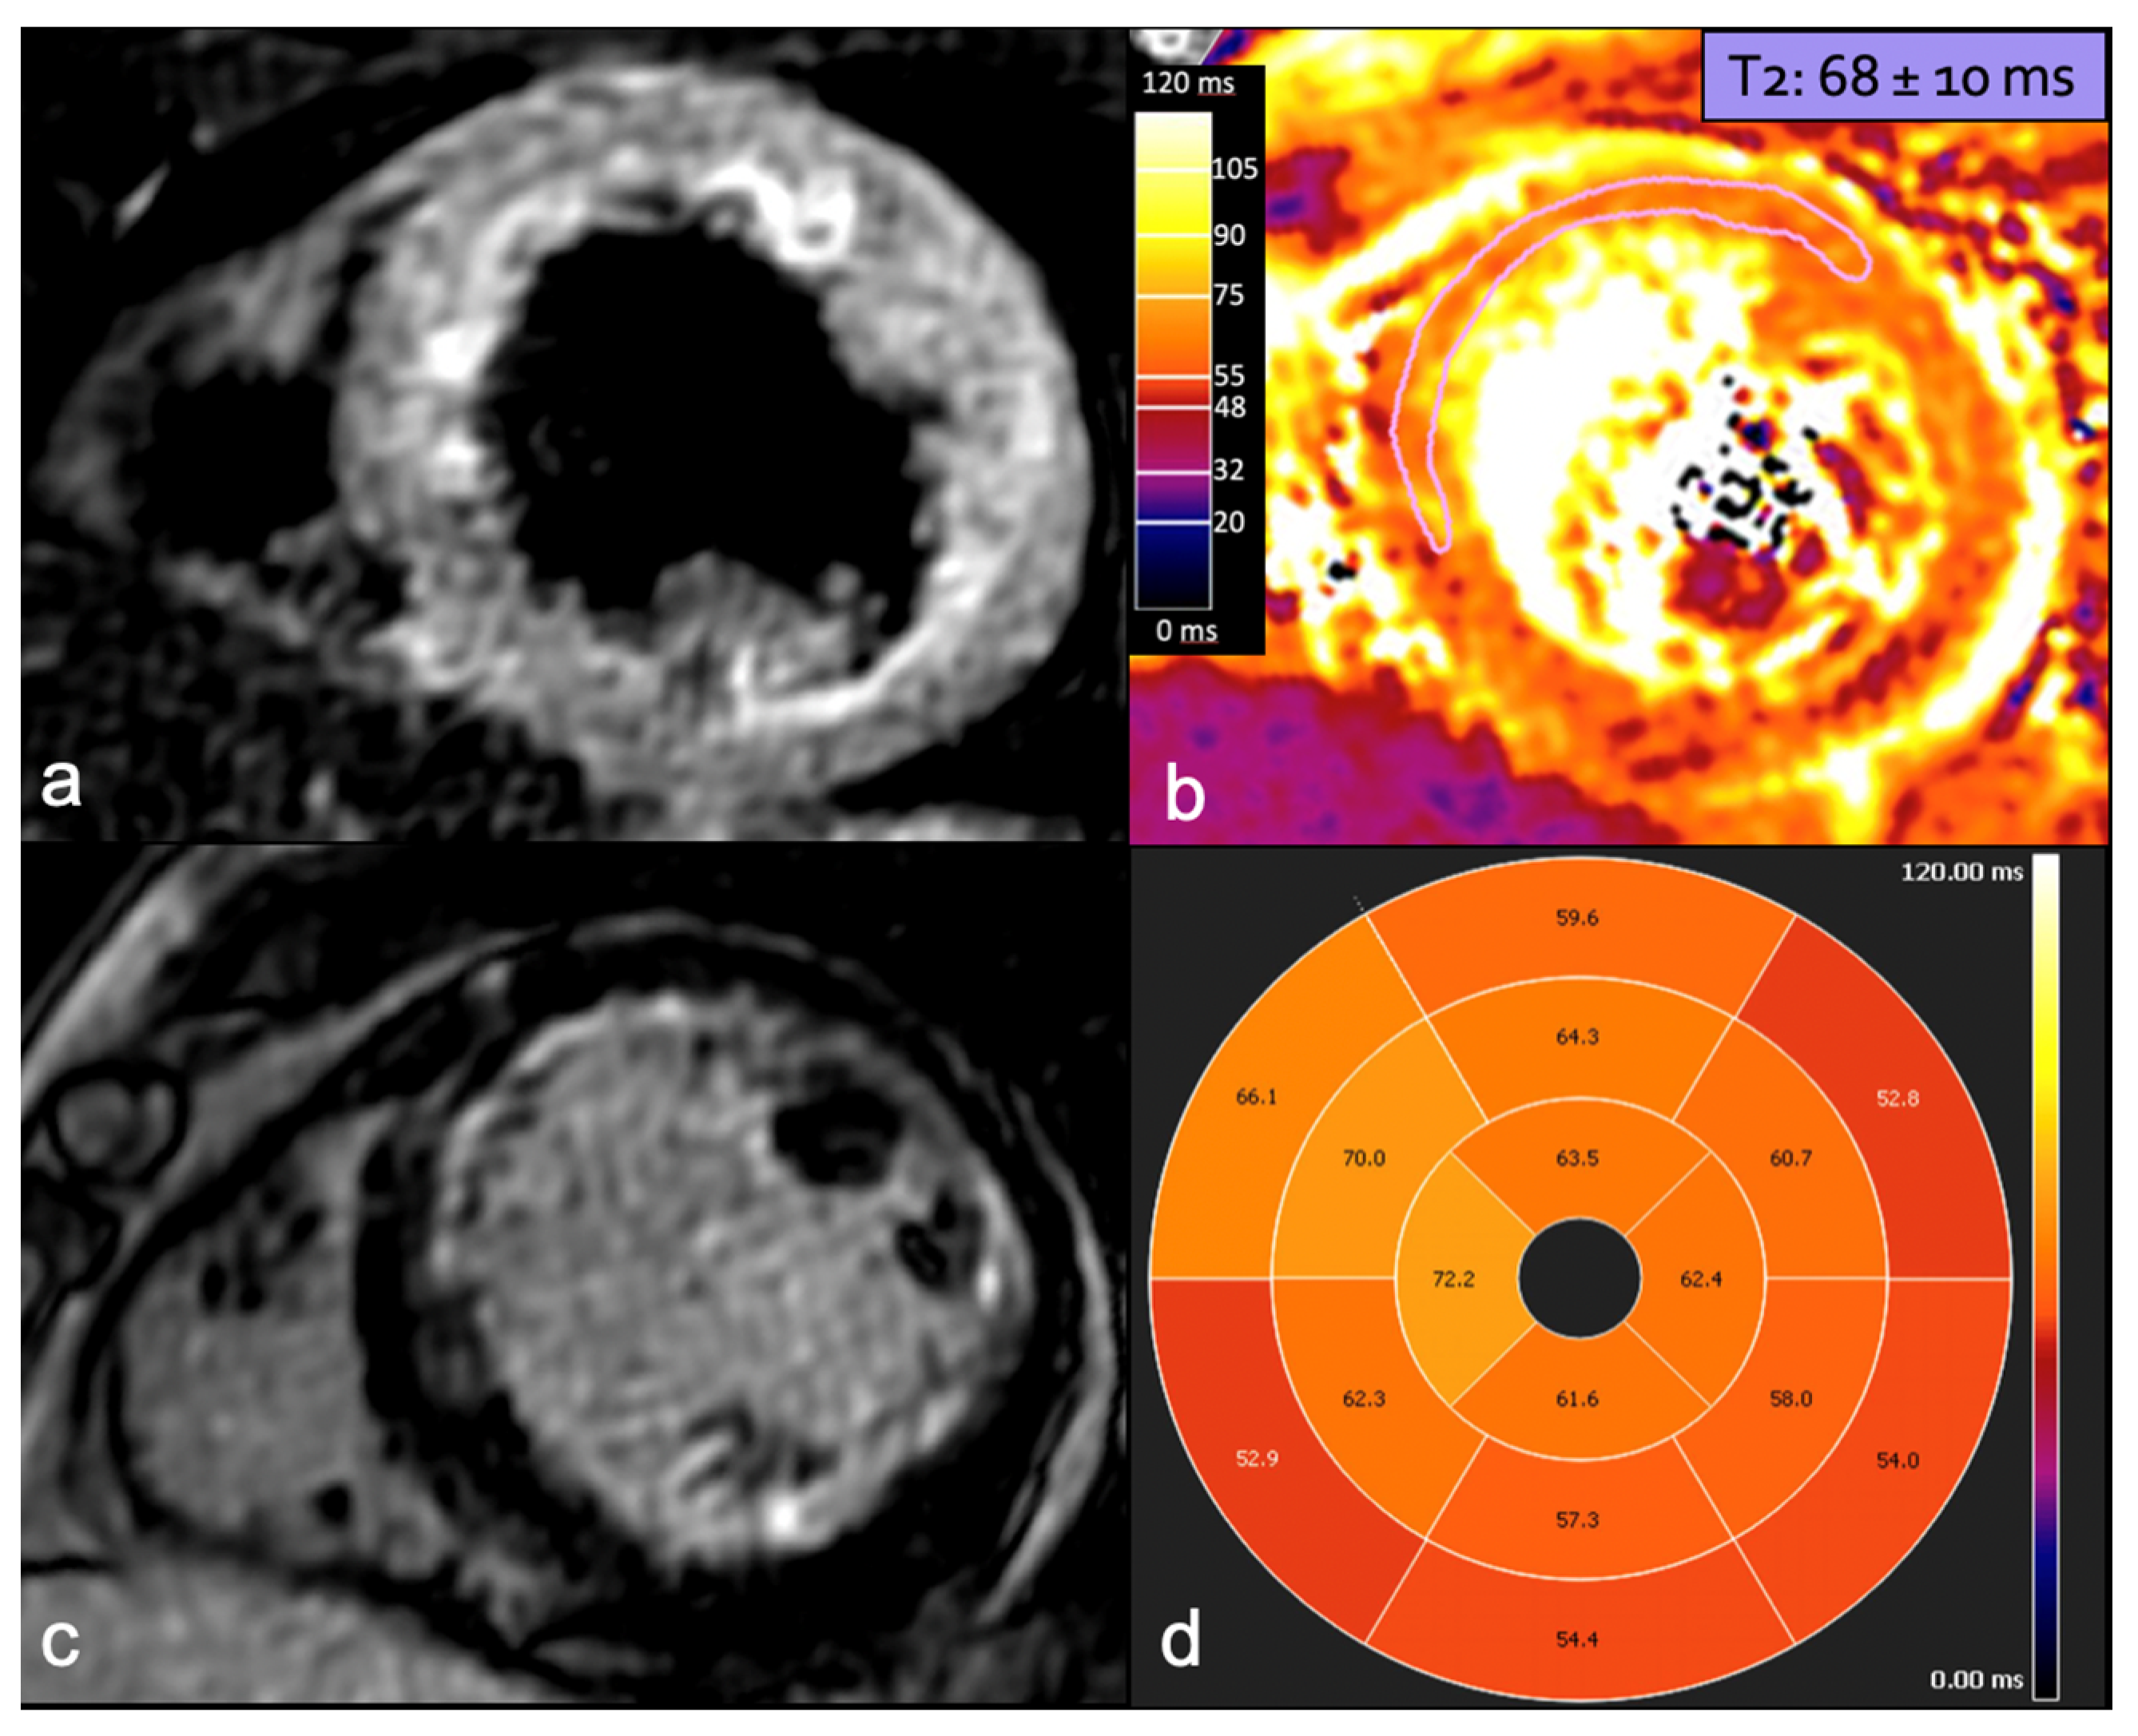

CMR: A Key to Diagnostic and Prognostic Insights

- Liang, Y.D.; Xu, Y.W.; Li, W.H.; Wan, K.; Sun, J.Y.; Lin, J.Y.; Zhang, Q.; Zhou, X.-Y.; Chen, Y.-C. Left ventricular function recovery in peripartum cardiomyopathy: A cardiovascular magnetic resonance study by myocardial T1 and T2 mapping. J. Cardiovasc. Magn. Reson. 2020, 22, 2. [Google Scholar] [CrossRef] [PubMed]

- Prameswari, H.S.; Kamarullah, W.; Pranata, R.; Putra, I.C.S.; Undarsa, A.C.; Iqbal, M.; Dewi, T.I.; Kusumawardhani, N.Y.; Akbar, M.R.; Astuti, A. Meta-analysis of cardiac magnetic resonance in prognosticating left ventricular function in peripartum cardiomyopathy. ESC Heart Fail. 2024. [Google Scholar] [CrossRef]

- Nii, M.; Ishida, M.; Dohi, K.; Tanaka, H.; Kondo, E.; Ito, M.; Sakuma, H.; Ikeda, T. Myocardial tissue characterization and strain analysis in healthy pregnant women using cardiovascular magnetic resonance native T1 mapping and feature tracking technique. J. Cardiovasc. Magn. Reson. 2018, 20, 52. [Google Scholar] [CrossRef] [PubMed]